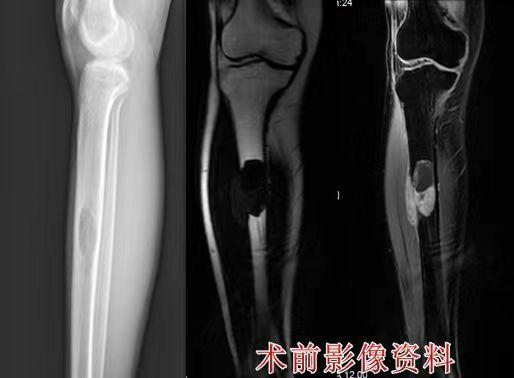

52143672_273d8b75-306e-4014-9709-aaa47f08e023.jpg

小敏(化名)术前影像资料 受访者供图